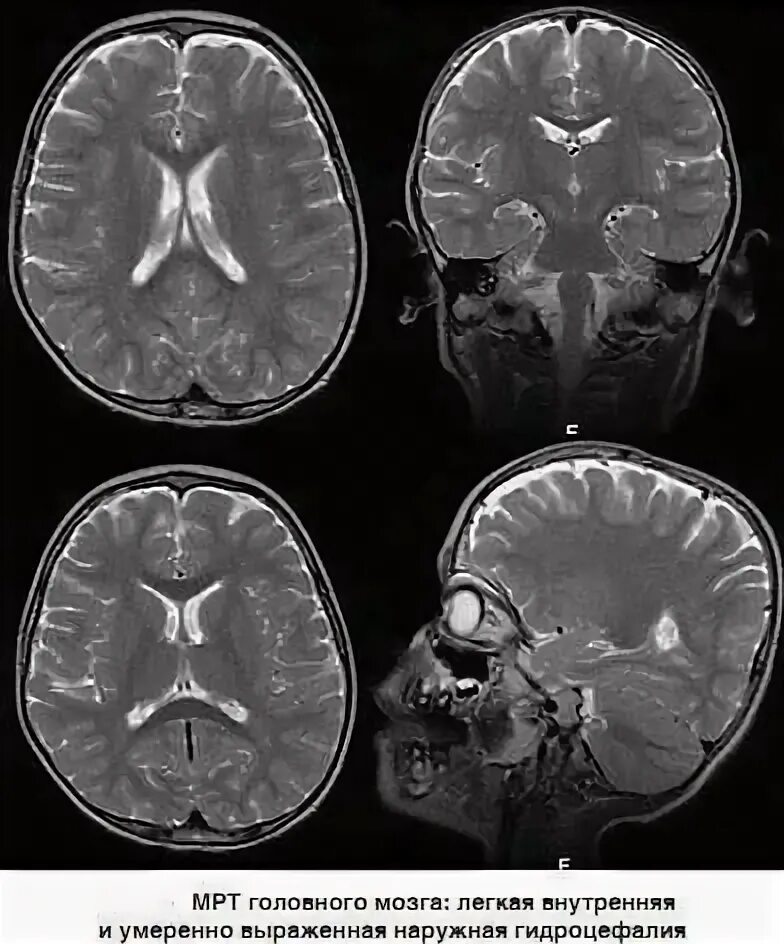

Умеренно выраженное внутреннее